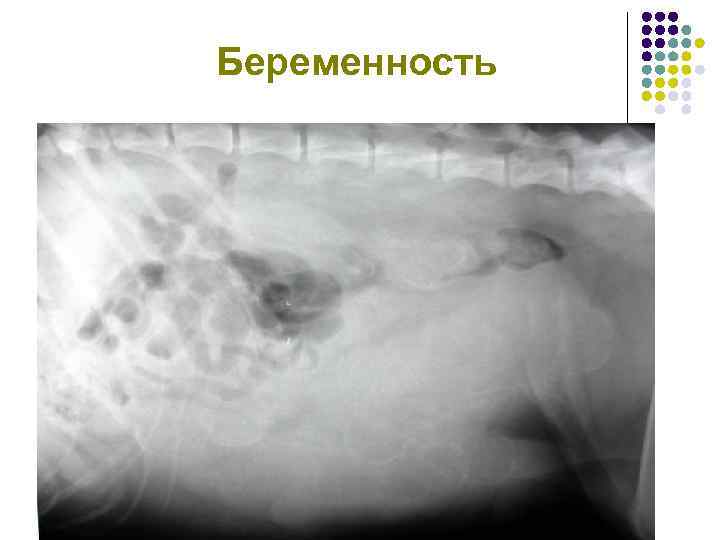

Беременность